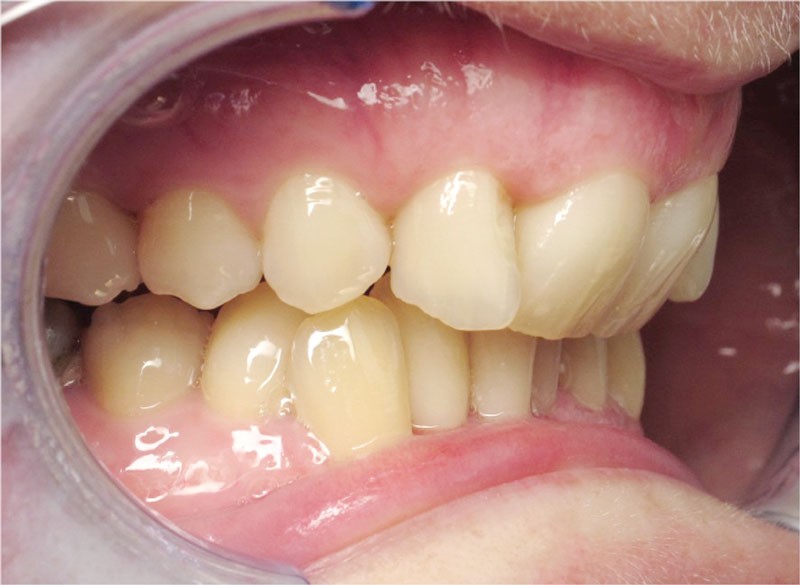

Conclusion

Les objectifs de traitement ont été remplis. Nous avons observé un excellent contrôle du torque et une absence de perte de l’occlusion postérieure grâce à la technique Insignia.